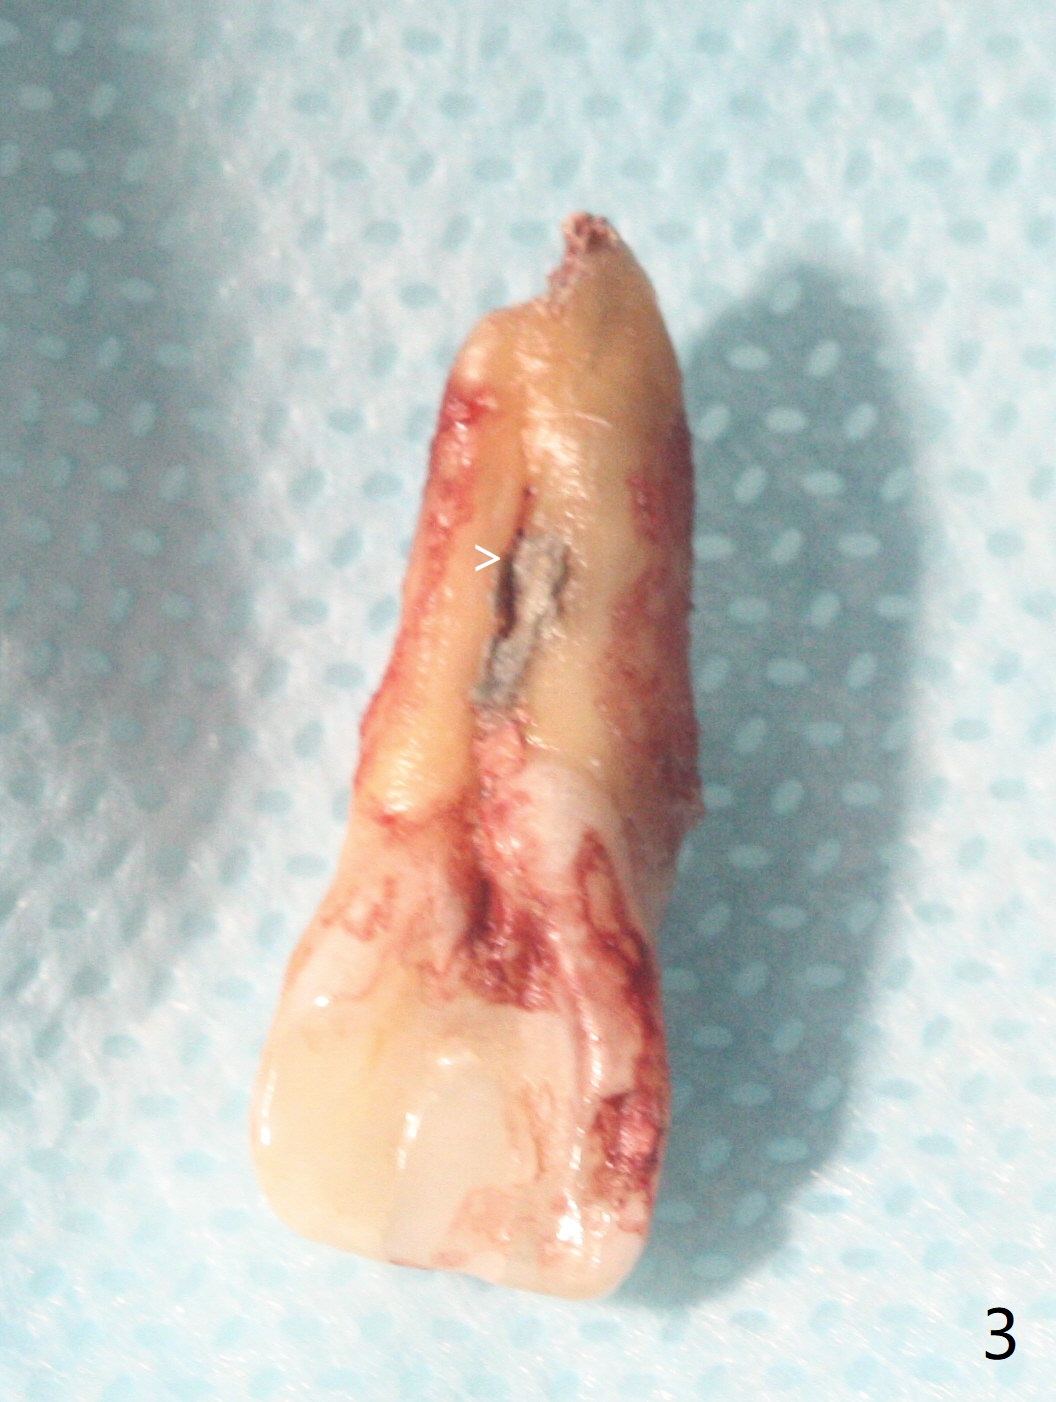

病人回来带来瘘道(图一),不过不会增加难度,病牙去除,它便自动消失。尽管颊侧骨壁完全失去,颊侧牙龈仍丰满(图二),为什么呢?第一,因为粗大牙根存在,第二两旁牙齿,牙槽骨撑着帐篷(侧切牙颊侧牙龈),第三,牙冠。为了防止术后牙龈塌陷,尽量不切开,即刻放置植体(牙根);由于前牙缘故,这次植体不能很大,所以植骨必须过度(over grafting),最后即刻制作临时牙冠,撑住牙龈。这就是所谓每个人进入角色。这个牙根有一种先天性畸形:dens in dent (图三(腭侧观):箭头)。尽管腭侧牙根畸形,腭侧骨壁吸收临床上并不严重,所以钻洞仍偏腭侧。当预定最后钻头还在钻洞时,填入大量粘性骨块(图四:*),细长植体还没有完全卡入鼻底(图五),最后好像可以(图六,七)。植体,骨粉入位(图八),最后临时牙冠出场(图九)。尽管植体小,术后一周临时牙冠仍然可以维持牙龈原有形状(emergency profile,图十:箭头(*:树脂强化牙冠固定))。图十一以不同角度显示瘘道缩小。术后三周取出有些松动的临时牙冠,骨粉虽然还没有被肉芽组织整合,但是显得正常,周围牙龈健康(图十二)。术后4个月牙龈形态正常(图十三),没有触痛;颊侧骨板轻度凹陷(图十四);骨粉仍在原位(图十五)。术后7个月骨粉仍在原位(图十五,十六,但是冠部密度减低(可能骨粉流失,需要牙周或者树脂敷料保护)),没有螺纹暴露。但是牙冠边缘暴露,说明牙龈收缩(图十七,与图十三对比),颊侧骨板仍塌陷(图十八)。插入龈线取得多个目的:修整基台边缘,取模,颊侧牙龈推向颊侧,有利于即将衬里牙冠龈缘进入龈下(图十九)。取模后牙冠边缘(图二十:<)衬里,然后修整,变窄,以便插入龈下,促进颊侧牙龈下降(图二十一,二十二)。术后8个月牙冠粘固前牙龈健康(图二十七,八),牙冠(图二十九)固位后,病人满意(图三十),咬合调整(图三十一),注意腭侧粘固粉流出通道(<)。